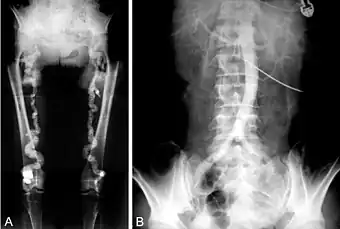

- Monckeberg's arteriosclerosis or medial calcific sclerosis is seen mostly in the elderly, commonly in arteries of the extremities.[11]